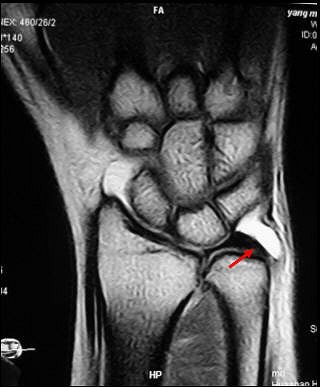

![]() |

| A 19-year-old woman with noncommunicating tear of triangular fibrocartilage at ulnar insertion in right wrist due to fall off skateboard five months before examination. Arthroscopy showed communicating tear of triangular fibrocartilage at this location. Coronal T1-weighted image obtained with fat-saturated spin-echo sequence (TR/TE, 525/15) shows noncommunicating defect (arrow) in ulnar attachment of triangular fibrocartilage. |